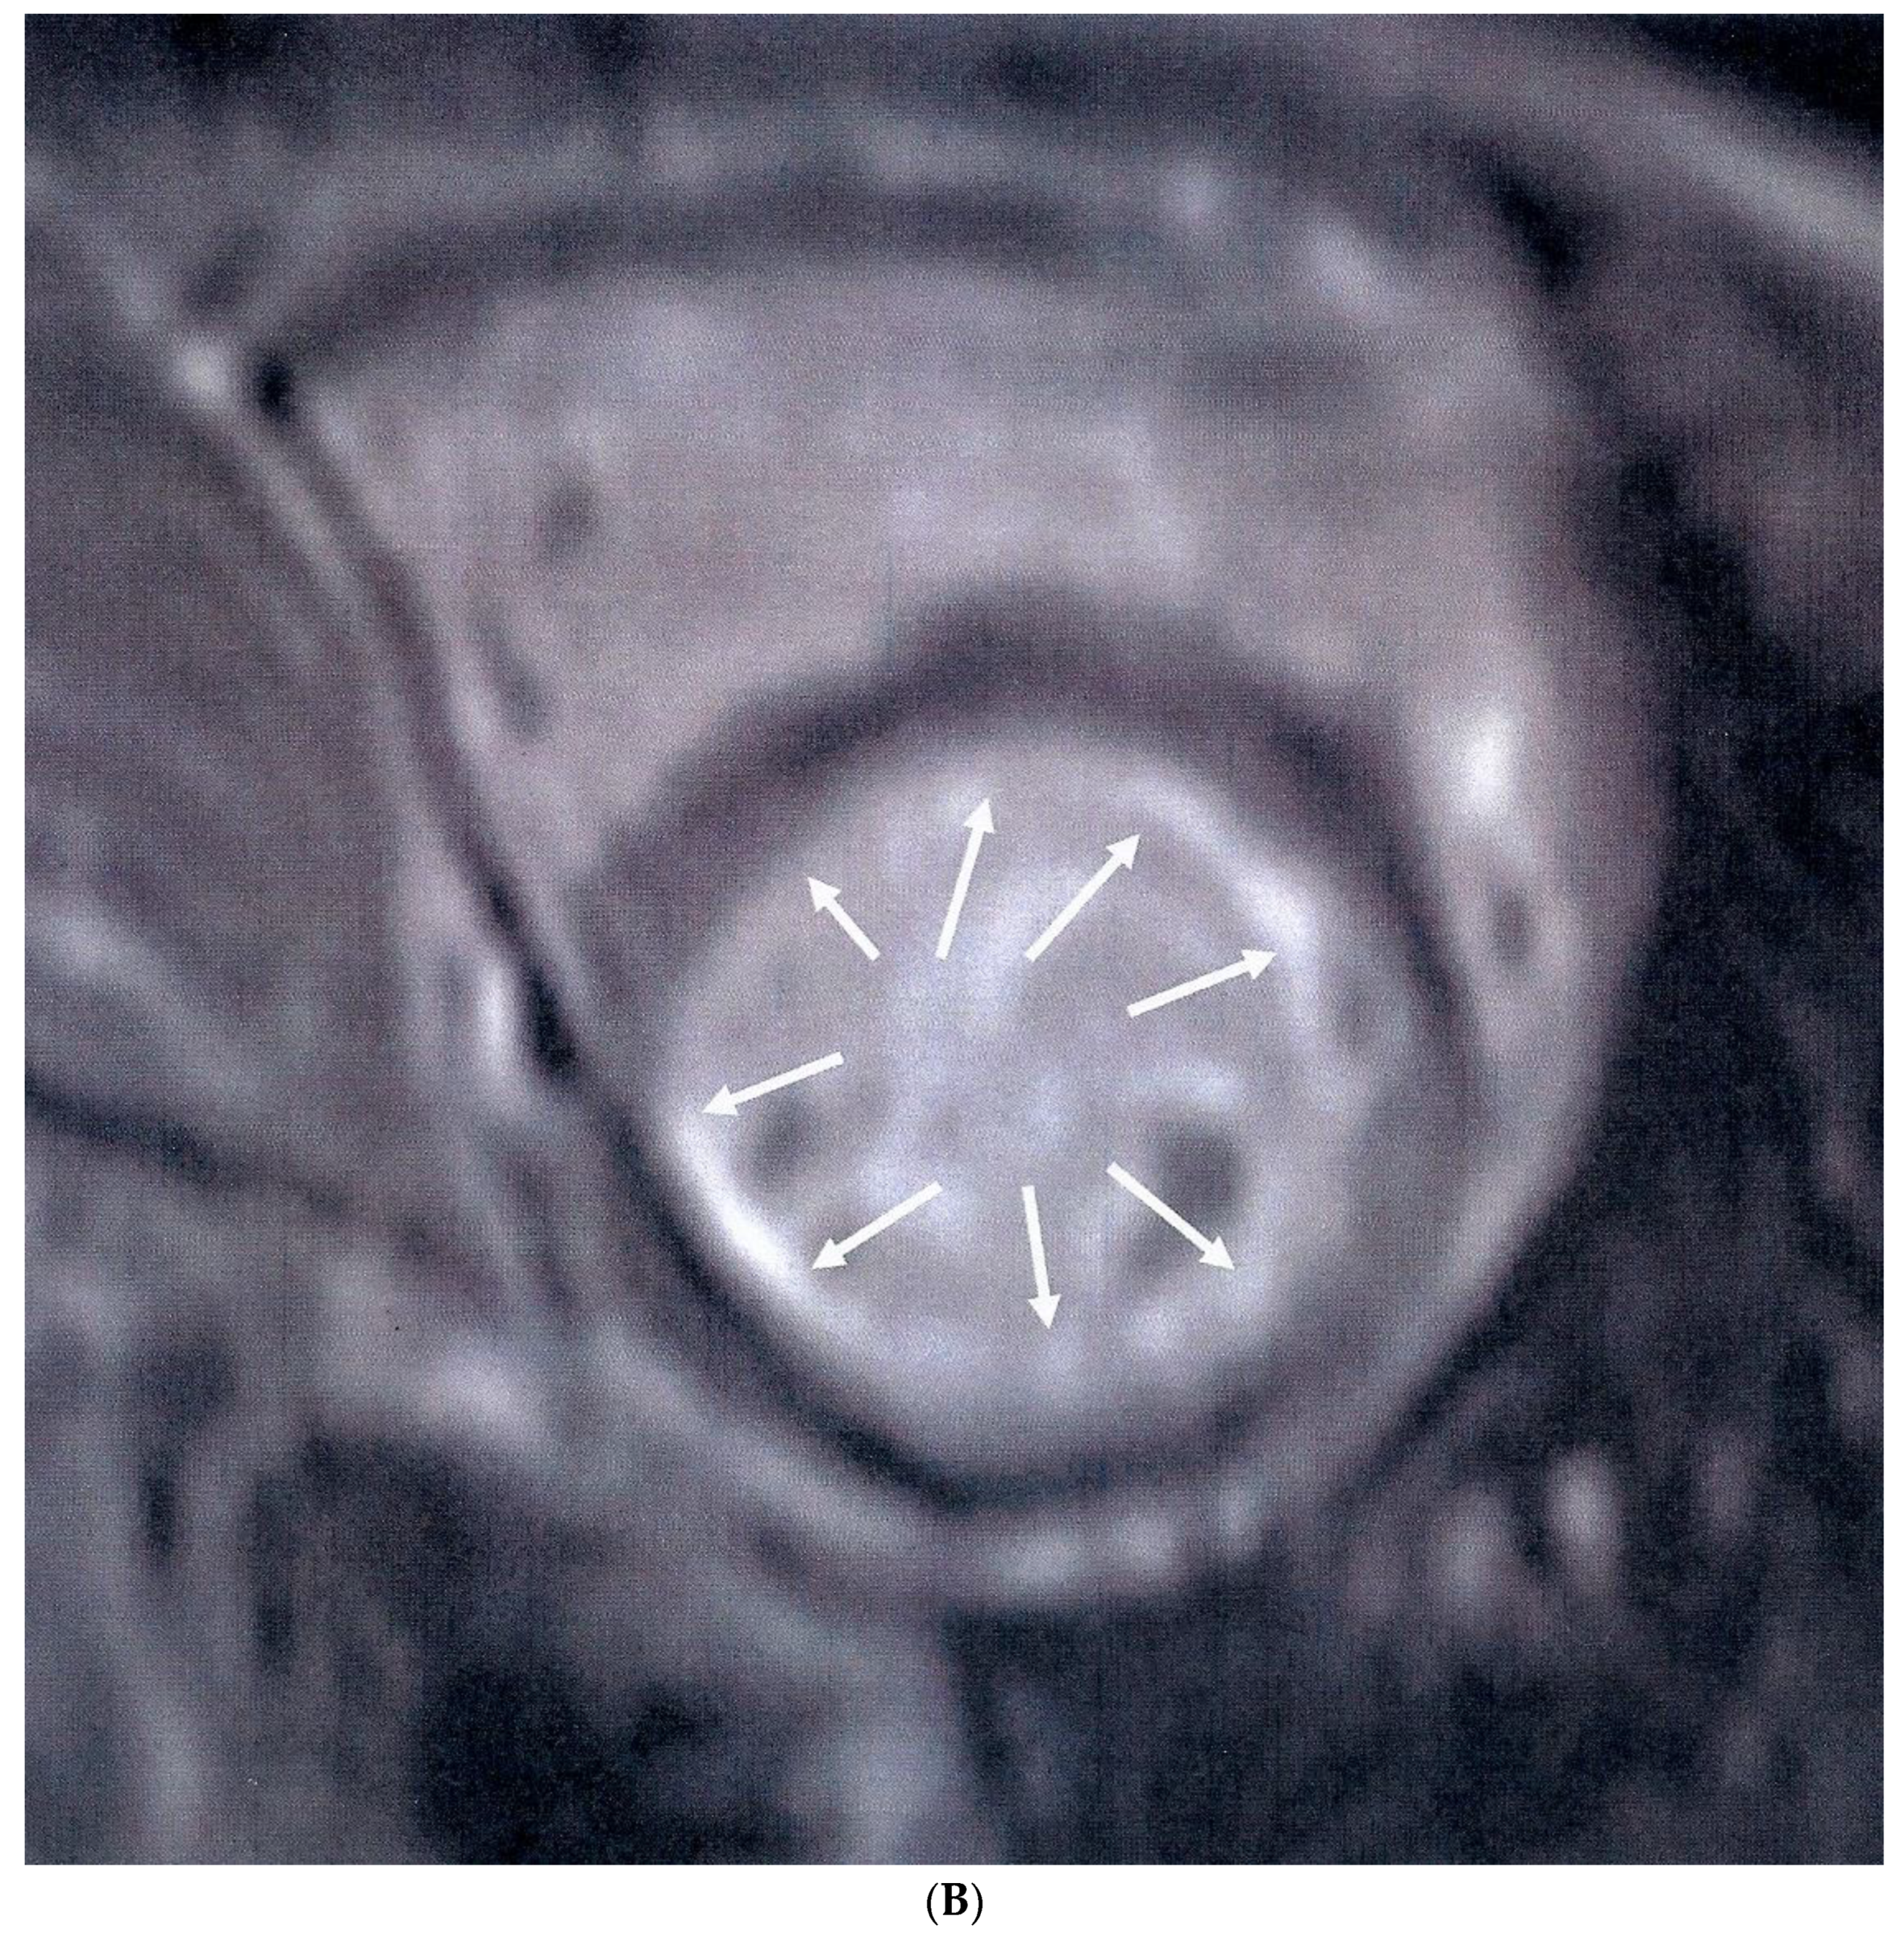

Median MPRI was significantly lower in APS patients compared to healthy controls [1.48 (0.9–1.9) vs. 2.7 (2.2–3.2), p < 0.001]. Sixteen (36%) APS patients had visible areas of myocardial scar, expressed as LGE, compared to none of the healthy controls (p < 0.001). Myocardial scar following the distribution of coronary arteries was identified in nine (20%) patients (five in the anteroseptal and four in the inferolateral LV wall) (Figure 1A), while diffuse subendocardial fibrosis (DSF) (Figure 1B) was identified in seven (16%) patients. In patients with a positive LGE, the median LGE values expressed as percentage of LV mass were 4.5 (3.5–7.5). Coronary angiography was performed in 12 of the 16 APS patients with positive LGE, with macrovascular (obstructive) CAD identified only in two patients, one of which subsequently underwent angioplasty of the left anterior descending artery. Three of 10 patients with otherwise normal coronary angiography findings had abnormal LVEF values (<55%) and concomitant low MPRI values below the median of the APS group (<1.48).

Figure 1. (A) Short-axis inversion recovery sequence showing septal myocardial scar (arrows), following the distribution of the left anterior descending artery, indicative of myocardial infarction. (B) Short-axis inversion recovery sequence showing diffuse subendocardial scar (arrows) due to microvascular disease.